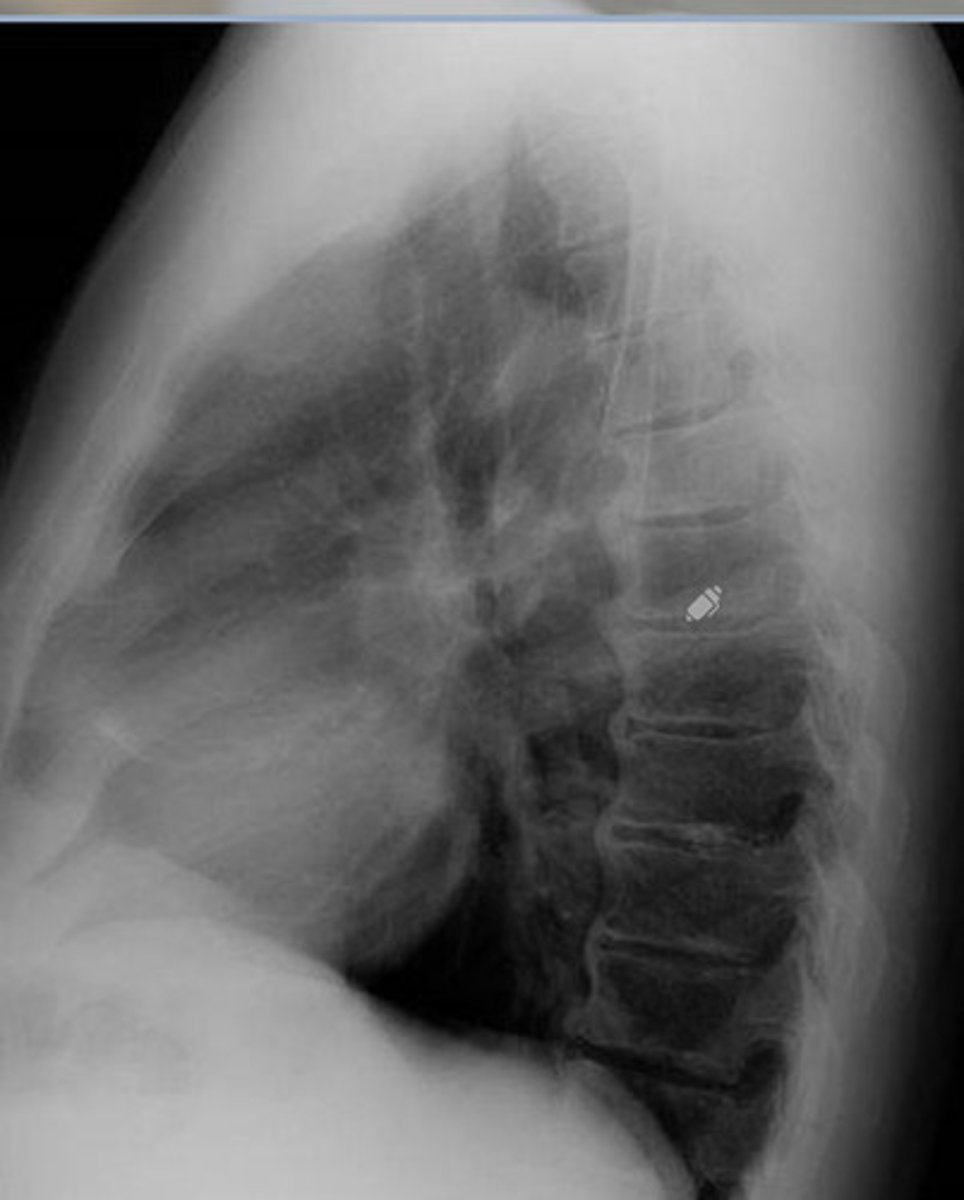

DISH/AH

What is this image showing?

Ossification of the PLL

Laminectomy

What is the pink?

What happened to there spinous processes?

Ossification of PLL

What is the blue?

Can cause cord stenosis

What is so dangerous of OPLL (ossification of PLL)?

AH

OPLL

What is the green?

What will cause the cord herniation

Cervical

What part of the spine is OPLL mc in?

OALL (if OALL is present, always check PLL)